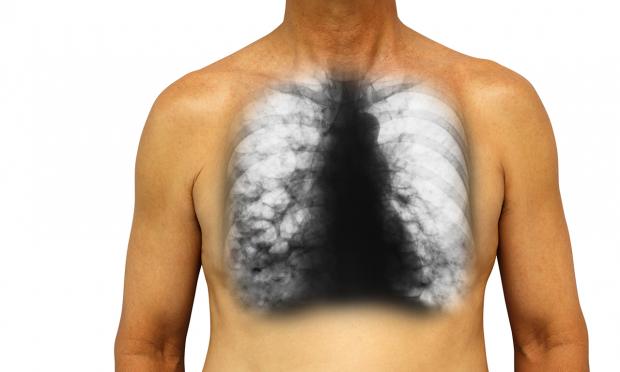

Vol 209, Issue 4: 20 August 2018. Dr Simone Visser and Clinical Associate Professor Lucy Morgan are respiratory physicians at RPA and Concord Repatriation General, respectively. They discuss the diagnosis and management of bronchiectasis. With MJA news and online editor, Cate Swannell